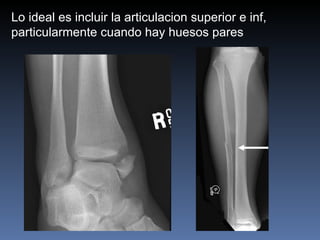

Lo ideal es incluir la articulacion superior e inf, particularmente cuando hay huesos pares

Lo ideal esincluir la articulacion superior e inf, particularmente cuando hay huesos pares